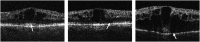

Purpose: To assess associations between visual acuity (VA) and the status of the photoreceptor inner segment-outer segment (IS-OS) junction in a subset of patients in the Standard Care vs COrticosteroid for REtinal Vein Occlusion (SCORE) Study.

Methodology: High-resolution time domain optical coherence tomography (OCT) scans of study eyes from a single site participating in the SCORE Study were evaluated. Integrity of the IS-OS junction in the central subfield was evaluated using a three-step scale: absent, abnormal or normal. Associations of the IS-OS status with ETDRS VA letter score and center point thickness (CPT) were investigated.

Results: Baseline OCTs of 42 eyes were evaluated. The IS-OS junction was absent in 30 (71%) and abnormal in 12 (29%). At month 12, the IS-OS junction was absent in 18 (43%), abnormal in 12 (28%), and normal in 12 (28%) eyes. At baseline, IS-OS status was significantly associated with CPT, but not with VA. At month 12, IS-OS status was significantly associated with CPT and VA, that is, absent or abnormal IS-OS was associated with increased CPT and worse VA. Change in IS-OS status was not associated with change in CPT (P=0.8). Worsening of IS-OS status was associated with loss of VA and improvement in IS-OS status to normal was associated with gain in VA (P=0.03).

Conclusion: In this data set with long-term follow-up of OCTs as part of the SCORE Study, there is a correlation between change in IS-OS status and VA. This supports further evaluation of outer retinal morphology in larger data sets.